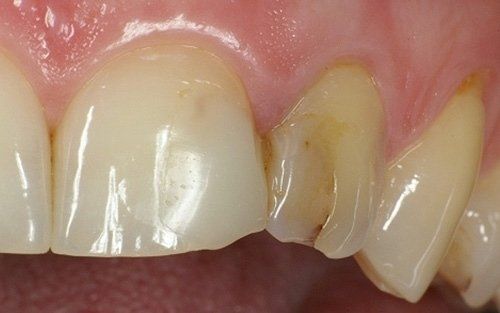

I restauri hanno subito una subito un intenso degrado sia nella forma che nel colore

I denti risultavano tutti vitali e dunque si è proceduto con terapie dirette molto conservative

Qui raffigurato l'incisivo laterale di destra, dopo la rimozione del vecchio restauro.